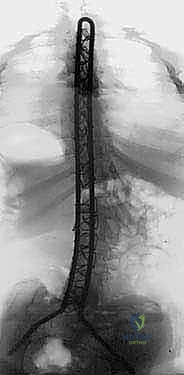

قضيب الوحدة هو غرسة معدنية طبية صلبة (مصنوعة عادة من الفولاذ المقاوم للصدأ أو التيتانيوم) تأخذ شكل حرف "U" المقلوب. يتم تشكيل هذا القضيب مسبقاً أو أثناء الجراحة ليتطابق مع الانحناءات الطبيعية المطلوبة للعمود الفقري (الحداب الصدري والقعس القطني).

1. التثبيت بالأسلاك (Sublaminar Wires): بدلاً من البراغي، يتم استخدام أسلاك معدنية مرنة وقوية تمرر بعناية فائقة تحت الصفيحة الفقرية (Lamina) لكل فقرة، ثم يتم ربطها وشدها حول قضيب الوحدة. هذا يوزع قوة التصحيح على مساحة واسعة من العمود الفقري، مما يقلل بشكل كبير من خطر كسر العظام أو فشل التثبيت.

2. تثبيت الحوض (Galveston Technique): يتم إدخال نهايتي حرف "U" (ساقي القضيب) عميقاً داخل عظام الحوض (الحرقفة - Ilium). هذا يربط العمود الفقري بالحوض ككتلة واحدة صلبة، مما يصحح ميلان الحوض فوراً ويسمح للطفل بالجلوس بشكل مستقيم.

بناءً على تشريح المريض، يتم ثني وتشكيل قضيب الوحدة المعدني ليعطي الظهر شكله الطبيعي. يتم وضع القضيب فوق العمود الفقري.

يبدأ الدكتور هطيف بربط الأسلاك حول القضيب وشدها تدريجياً وبطريقة هندسية محسوبة. مع شد الأسلاك، يتم سحب العمود الفقري الملتوي ليصطف مع القضيب المستقيم، مما يصحح الجنف وميلان الحوض في آن واحد. يتم قص الأجزاء الزائدة من الأسلاك وثنيها للداخل بأمان.

لضمان نجاح العملية على المدى الطويل، لا يُكتفى بالتثبيت المعدني. يتم وضع طعوم عظمية (من عظام المريض نفسه التي أزيلت أثناء التحضير، أو من بنك العظام) على طول الفقرات. بمرور الأشهر، ستنمو هذه العظام وتلتحم لتشكل كتلة عظمية صلبة واحدة (Spinal Fusion)، مما يمنع انحناء الظهر مجدداً حتى لو فشلت المعادن.